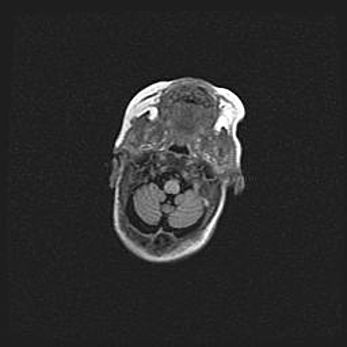

Подострая гематома правой гемисферы мозжечка.

Наружная гидроцефалия.

Возраст: 15 дней

Вес: 3100 г

Пол: женский

Окружность головы: 37 см

Срок гестации: 35-36 недель

При открытой наружной форме гидроцефалии у новорожденных расширяются и переполняются субарахноидные пространства.

Кровоизлияния в мозжечок имеют две клинико-анатомические формы: полушарные гематомы и кровоизлияния в червь.

К появлению этой патологии может привести: повреждения головного мозга, возникающие в результате асфиксии и гипоксии плода при беременности, или травмы во время родов. Редко гематома мозжечка может быть результатом первичной коагулопатии и сосудистой мальформации, диссеминированном внутрисосудистом свертывании, изоиммунной тромбоцитопении.